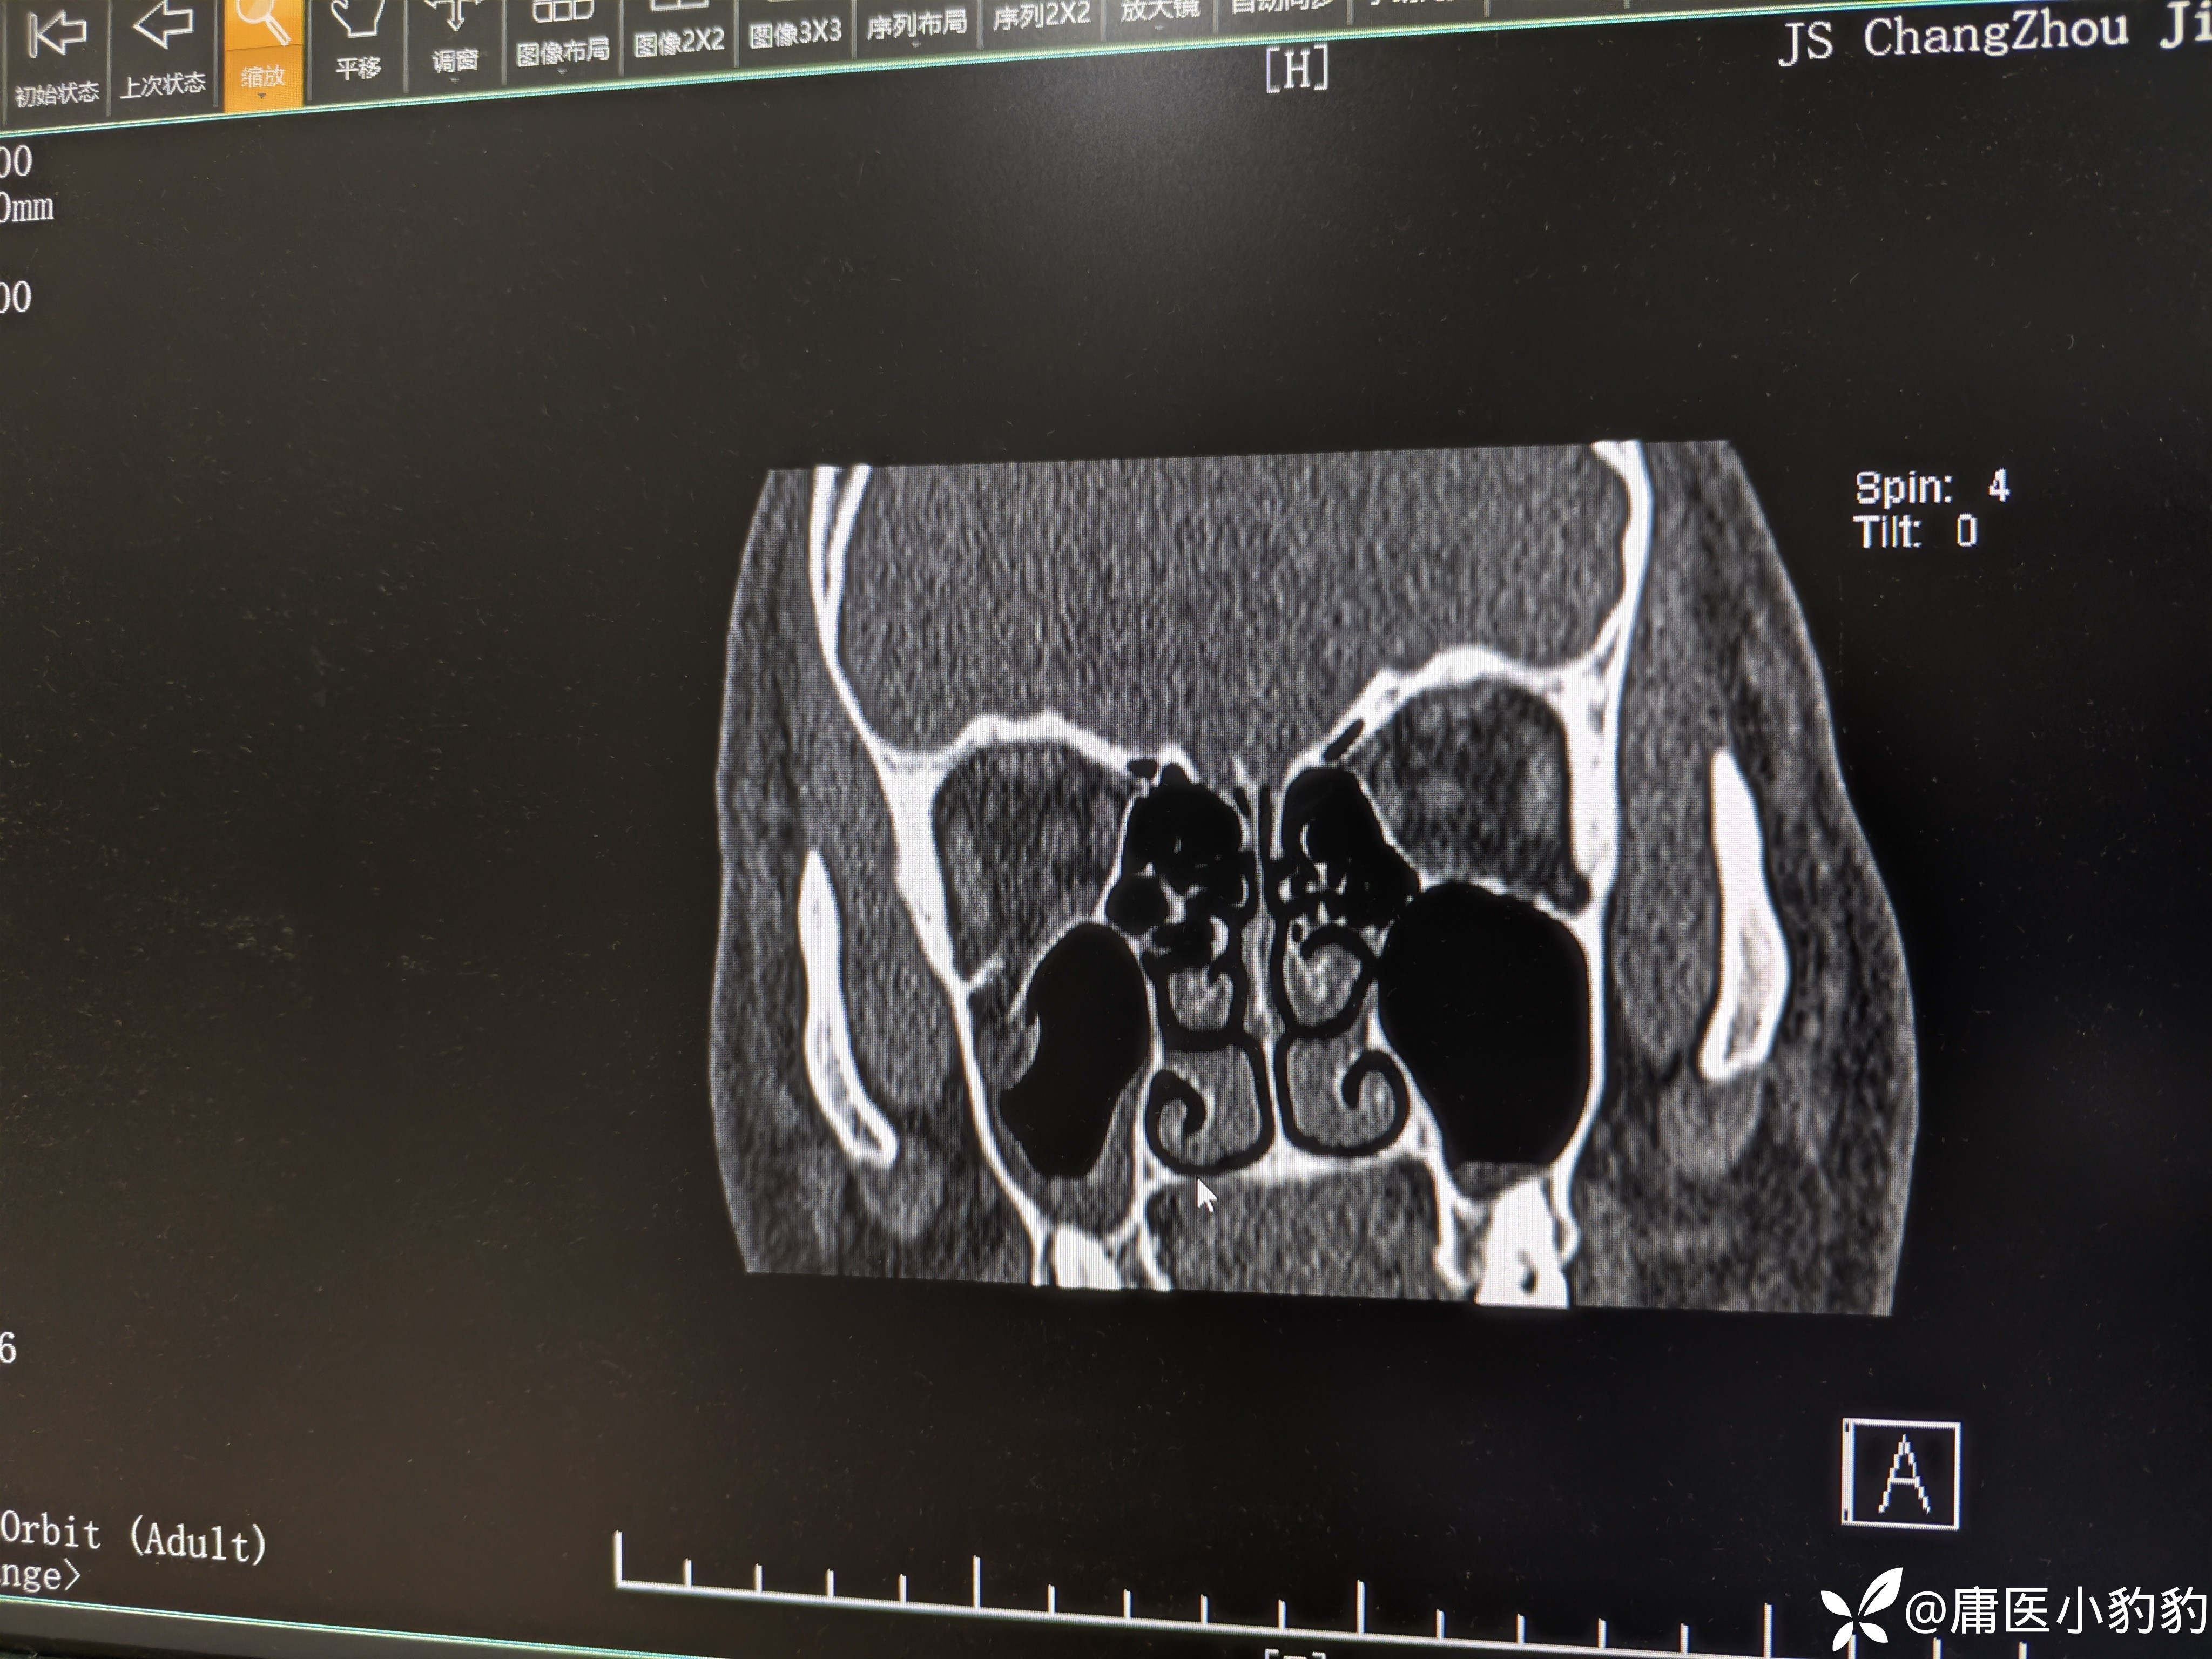

患者,男,26岁,五天前右面部外伤,右眼结膜下出血,主诉右眼视物模糊。眼眶CT示右上颌窦上壁骨折,右上颌窦内积血。眼科学检查示 矫正视力:右8.0/左1.0,眼压右18/左20,右眼视网膜震荡。无明显复视,重影,眼球运动未见明显受限,未行眼球牵拉试验。目前正在甘露醇+激素治疗观察。请问各位眼科的同门对该患者后续的治疗方案有何建议?